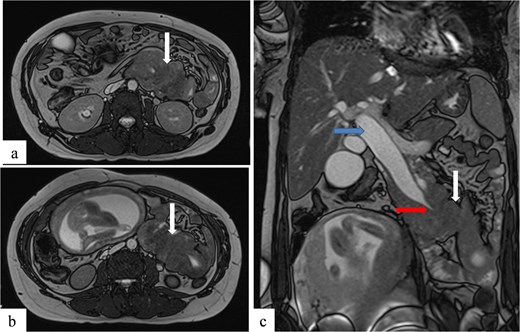

Due to the acute presentation and unavailability of emergency magnetic resonance imaging (MRI), a contrast-enhanced computed tomography (CT) scan of the abdomen was performed with strict fetal protection measures (lead apron, low-dose protocol). The pancreas appeared normal with no signs of inflammation, necrosis, or peripancreatic fluid. Unexpectedly, the scan revealed a duodenojejunal intussusception, likely originating from the fourth portion of the duodenum (D4), involving invagination of a proximal jejunal loop (Fig. 1). A typical pseudokidney sign was observed on sagittal reconstructions (Fig. 2). There was no identifiable lead point such as a mass or polyp. The intussusception was seen tractioning the distal common bile duct, leading to marked extra- and intrahepatic bile duct dilatation (Fig. 3).

Axial contrast-enhanced CT image showing a duodenojejunal intussusception (arrow), originating from the fourth portion of the duodenum and involving invagination of a proximal jejunal loop.

Sagittal contrast-enhanced CT images (a, b) showing the duodenojejunal intussusception with a pseudokidney appearance (arrows).